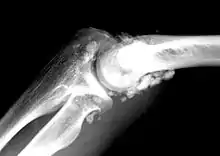

Radiographie d’un coude atteint de chondromatose.

- Pathologie rhumatismale bénigne touchant les articulations synoviales.

La chondromatose synoviale (primitive ou idiopathique) est caractérisée par la formation de multiples nodules de cartilage hyalin sous la membrane synoviale.

— (H. Brassens, X. Leroy, G. Wavreille, C. Canella, H. Migaud, A. Cotten, Chondromatose synoviale, www.em-consulte.com, 2010)